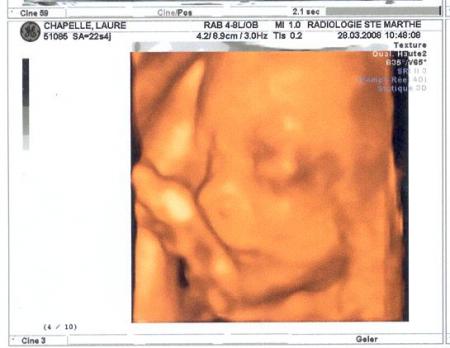

en 3 D.

27/11/2008 20:00 par lauremanulucas

nous sommes toujours à la 1ère écho.